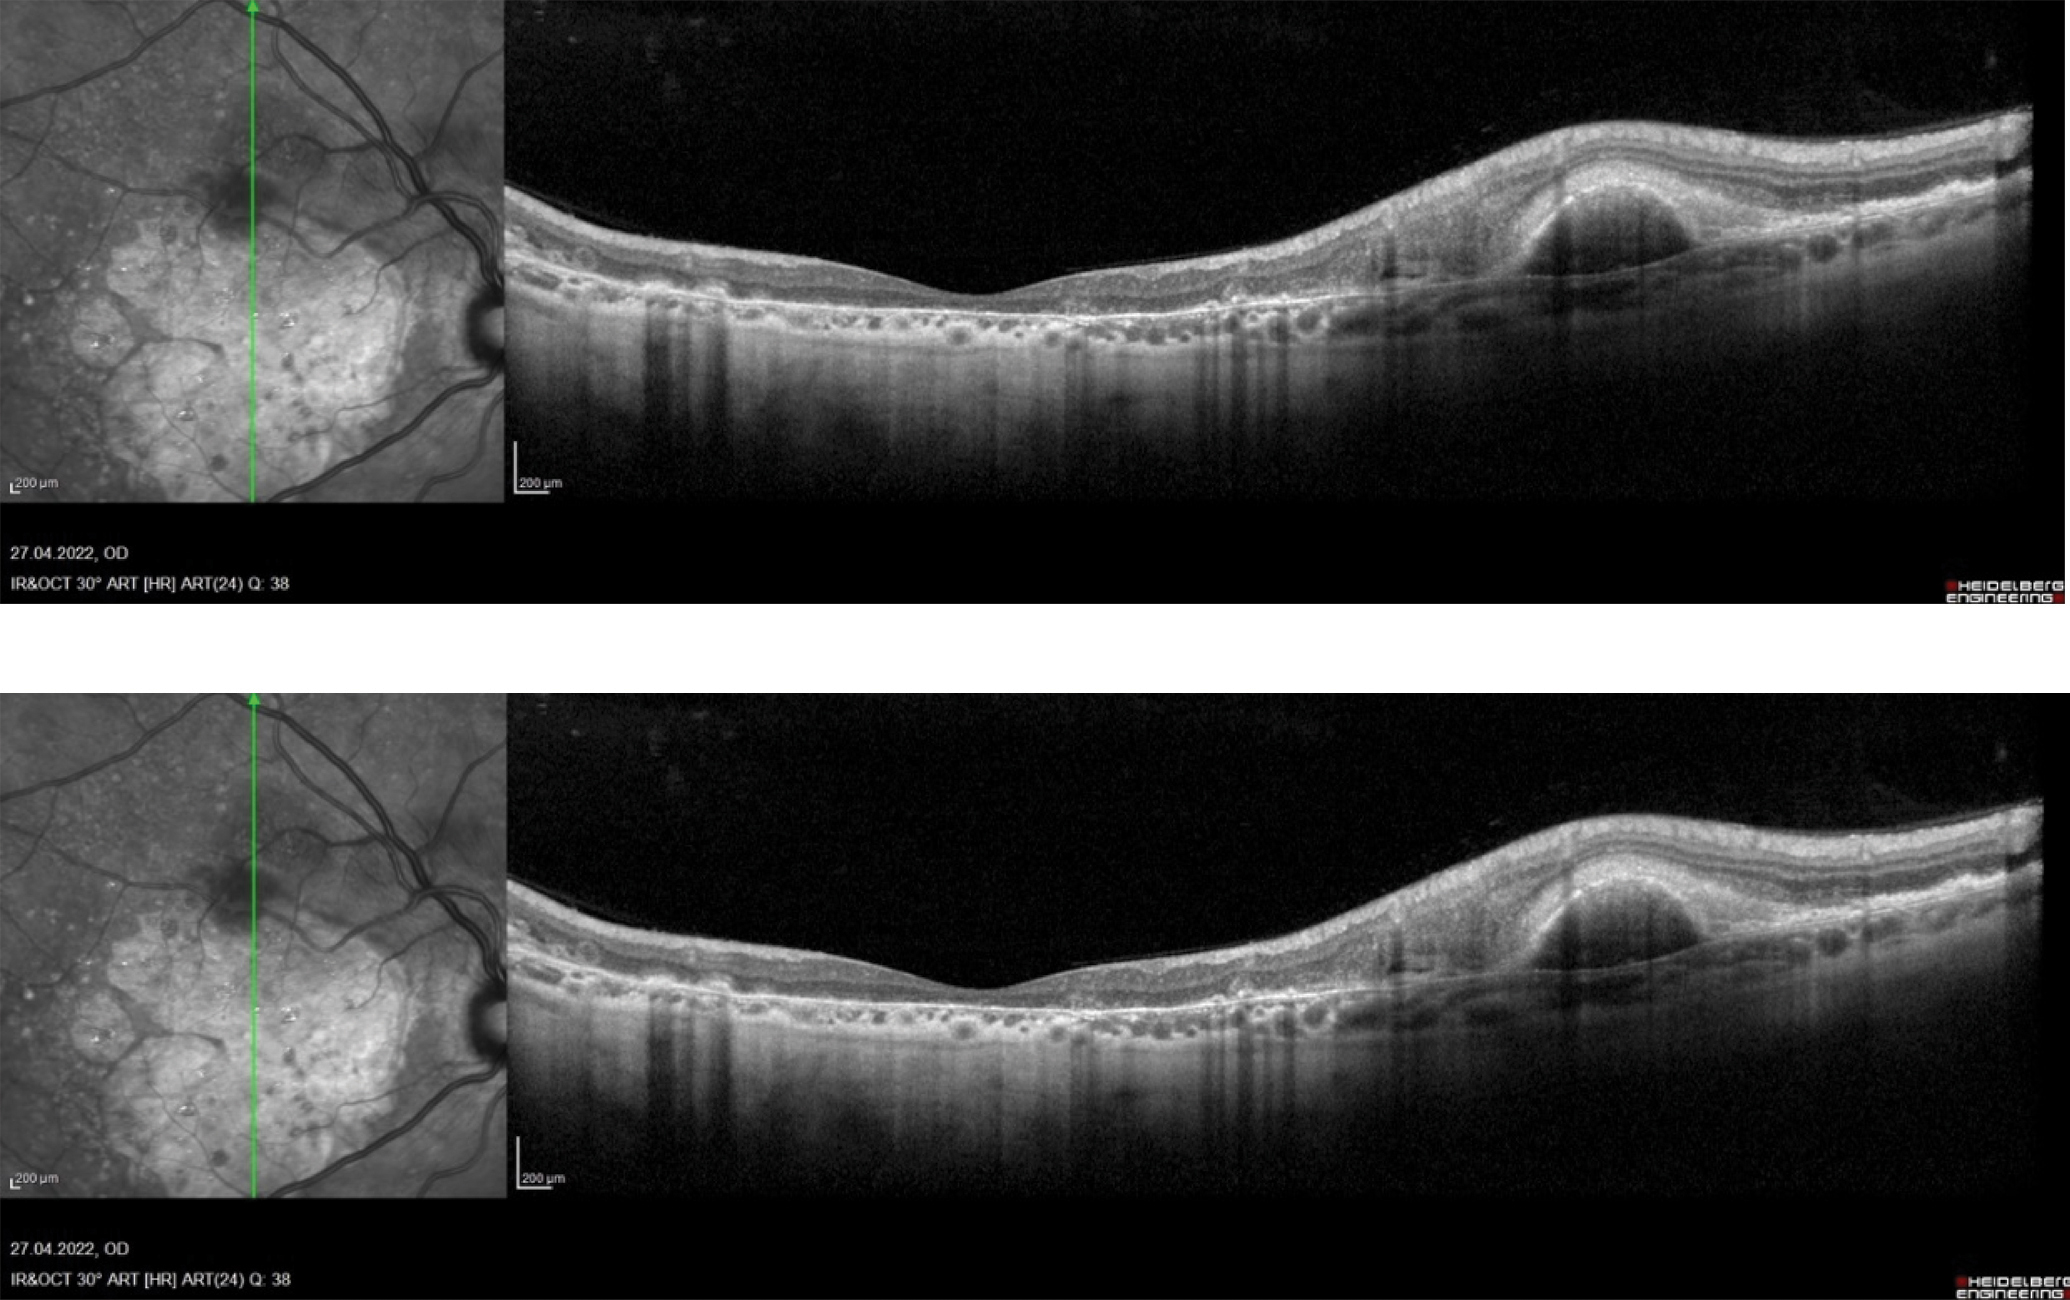

Для демонстрации результатов представляем клинический случай идиопатического макулярного разрыва пациентки В., подтвержденного при ОКТ-сканировании (рисунок 2). Результатом проведенного фиксационного теста является верхне-левая локализация предпочтительного ретинального локуса (рисунок 3).

Рисунок 2. ОКТ-сканирование левого глаза пациента В. с идиопатическим макулярным разрывом.

Figure 2. OCT scan of the left eye of patient B. with idiopathic macular hole.

В качестве клинического примера, иллюстрирующего локализацию ПРЛ при возрастной макулярной дегенерации, можно привести данные наблюдения за пациенткой А., 58 лет, с влажной формой ВМД правого глаза и сухой формой ВМД левого глаза. Полное отсутствие слоя пигментного эпителия и эллипсоидной зоны фоторецепторов, являющихся причиной абсолютной скотомы, подтверждено на ОКТ-сканах (рисунки 4а, 4б). При определении точки фиксации правого глаза была выявлена верхне-левая перифовеолярная область сетчатки, отвечающая за фиксацию взора (рисунок 5а). Точка фиксации на левом глазу была обнаружена в верхне-левой части перимакулярной области (рисунок 5б).

Рисунок 4. ОКТ-сканирование обоих глаз пациентки А.: а) ОКТ-признаки неоваскулярной формы возрастной макулярной дегенерации на правом глазу; б) ОКТ-признаки географической атрофии в исходе сухой формы возрастной макулярной дегенерации на левом глазу.

Figure 4. OCT scan of both eyes of patient A.: a) OCT signs of neovascular form of age-related macular degeneration in the right eye; b) OCT signs of geographic atrophy as the outcome of the dry form of age-related macular degeneration in the left eye.